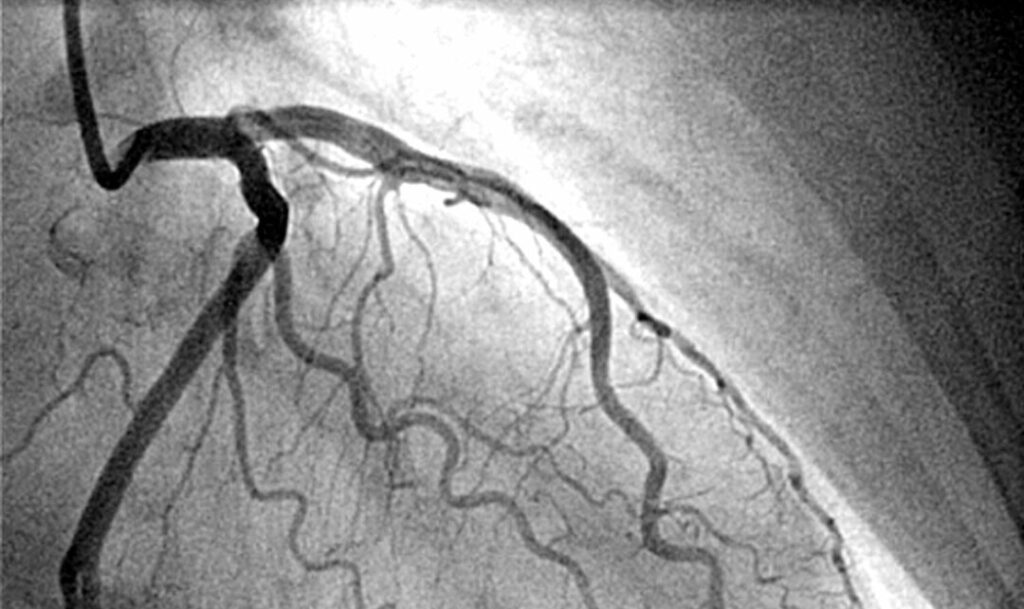

Coronary Angiography (or Coronary Angiogram) is an imaging procedure that uses a special dye and X-ray technology to visualize the coronary arteries. By injecting a contrast dye into the heart’s arteries, doctors can see:

- How well blood flows through the arteries

- Presence of blockages or narrowing (stenosis)

- Exact percentage of blockage

- Condition of the heart chambers and valves

- Abnormalities in blood vessels

This procedure helps in diagnosing conditions like coronary artery disease (CAD), heart attack, chest pain (angina), congenital heart issues, and other structural problems. It is considered the gold standard for detecting blockages

Contrast Dye Injection:

Once the catheter is properly positioned, your doctor injects contrast dye through it into your coronary arteries. You might experience a warm, flushing sensation throughout your body when the dye is injected—this is completely normal and lasts only a few seconds. The dye makes your arteries visible on X-ray images.

Image Capture:

The X-ray camera rotates around you, taking pictures from multiple angles as the dye flows through your arteries. Your doctor may ask you to hold your breath briefly or take deep breaths at certain points. You’ll see the images on monitors in the room, and your doctor may explain what they’re seeing.